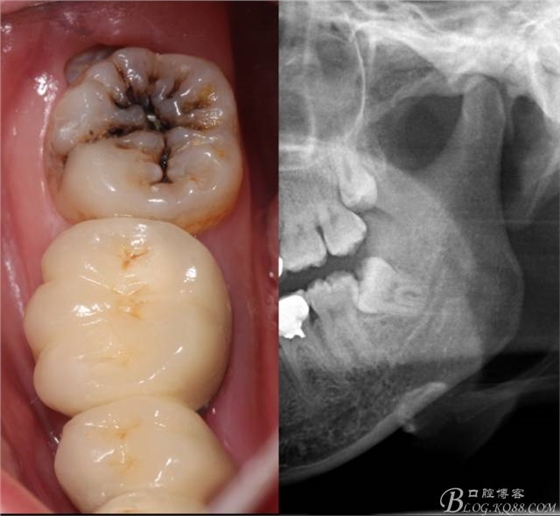

檢查:(1)37牙合面齲,卡探針. (2)38近中埋伏阻生

X全景片示38近中三類阻生,非融合根,近中根壓下頜管,37遠中鄰面中齲樣影像。

診斷:(1)37中齲 (2)38近中阻生